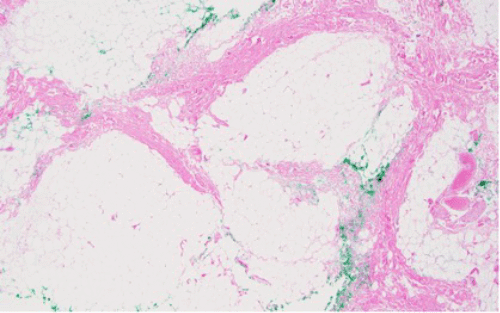

Figure 2. Immunohistochemical Stains of Soft Tissue Mass Biopsy. Published with Permission

H&E stain (40x original magnification) showing lobules of adipocytic cells in varying stages of maturation, separated by fibrous bands

At 40x magnification, an admixture of mature adipocytes, occasional lipoblasts (immature fat cells with vacuolated cytoplasm and scalloped nuclei), and a myxoid to fibrous stroma is highlighted